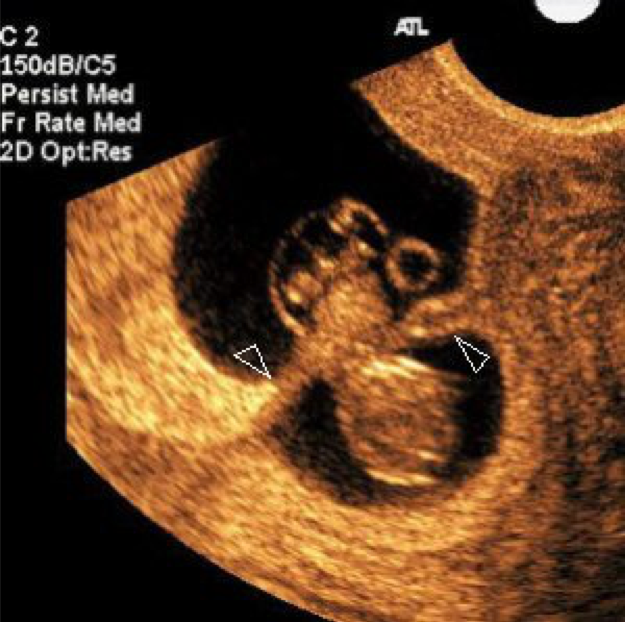

Ultrasound images of amniotic band syndrome and a lumbosacral

Recognizing Intraamniotic Bandlike Structures on Obstetric Ultrasound